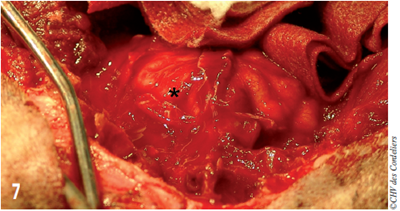

Afin de prétendre à des marges saines, le processus zygomatique de l’os frontal gauche est retiré. Le cerveau est alors exposé (photo 7).

Photo 7 : L’encéphale est exposé ; L’hémisphère droit est ici recouvert des méninges (étoile) ; elles seront réséquées pour analyse anatomo-pathologiques (marges profondes).